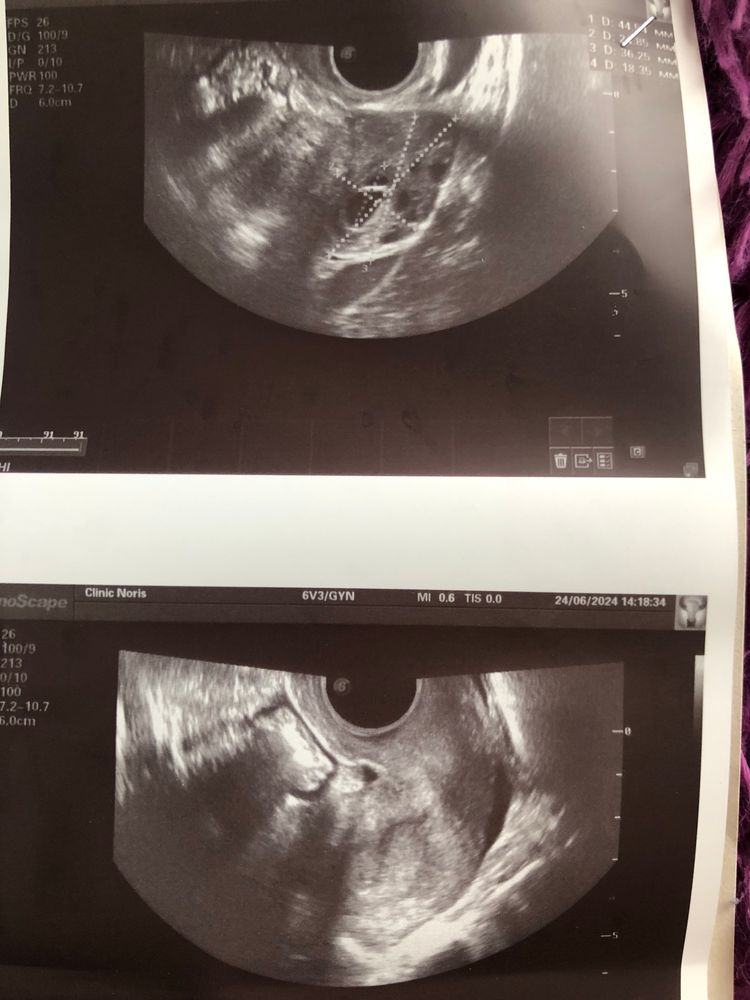

Гидроэхолакация

Визуализация эмбриона УЗИ в 7 недель